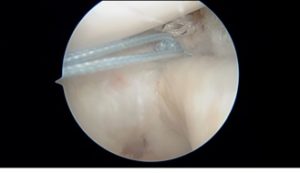

Shoulder anterior stabilization: arthroscopic